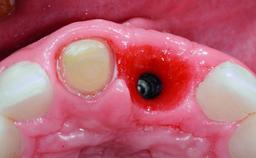

A healthy 28-year-old female patient presented for a consultation on treatment options to restore her upper right central incisor. At the clinical examination, the tooth responded to percussion and palpation. The gingiva was red and slightly swollen, with a mid-facial probing depth of 10 mm. The upper right lateral incisor showed no signs or symptoms, did not respond to exploration and percussion, and the vitality test was positive. The periapical radiograph revealed that tooth 11 had been endodontically treated, with no lesion evident at the apex. A small radiopaque calcified structure surrounded by a narrow radiolucent zone (3 × 3 mm) was present at the apex of tooth 12.

Bone Augmentation | Horizontal|Simultaneous |

Augmentation Materials | Autogenous chips|Xenogenous|Membrane |